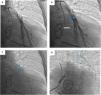

Device implantationPrior to hospital admission, patients were screened for COVID-19 infection. Our methodology for implanting the CardioMEMS™ sensor followed previous reports (Figure 2 and Videos - Supplementary File 1).5 Using sterile technique and local anesthesia, the femoral vein was cannulated with a 7-F sheath and upsized to a 12-F sheath. RHC was performed using a balloon wedge-pressure catheter (BWPC) for pressure assessment and estimation of cardiac output. A limited pulmonary angiogram was performed to identify an appropriate target. Ideally, a left posterior artery was selected, measuring at least 7 mm in diameter. Then, a 0.018-inch stiff guidewire (GW) was placed in the vessel and the BWPC was exchanged for the device delivery system. The CardioMEMS™ sensor, which is tethered to the end of the delivery catheter, was advanced over the GW and released into the target vessel. After removing the delivery catheter, PAP was measured again for device calibration. Hemostasis was achieved using the Perclose ProGlide™ vascular closure device (Abbott Scientific, IL, USA).

A Selective pulmonary angiogram is required to identify an appropriate-sized pulmonary artery branch. B Measurement of the target vessel (asterisk) at the desired implant location (over 7 mm of diameter). C Sensor on the delivery catheter prior to release (dotted circle). D Sensor (dotted circle) released in the desired location.